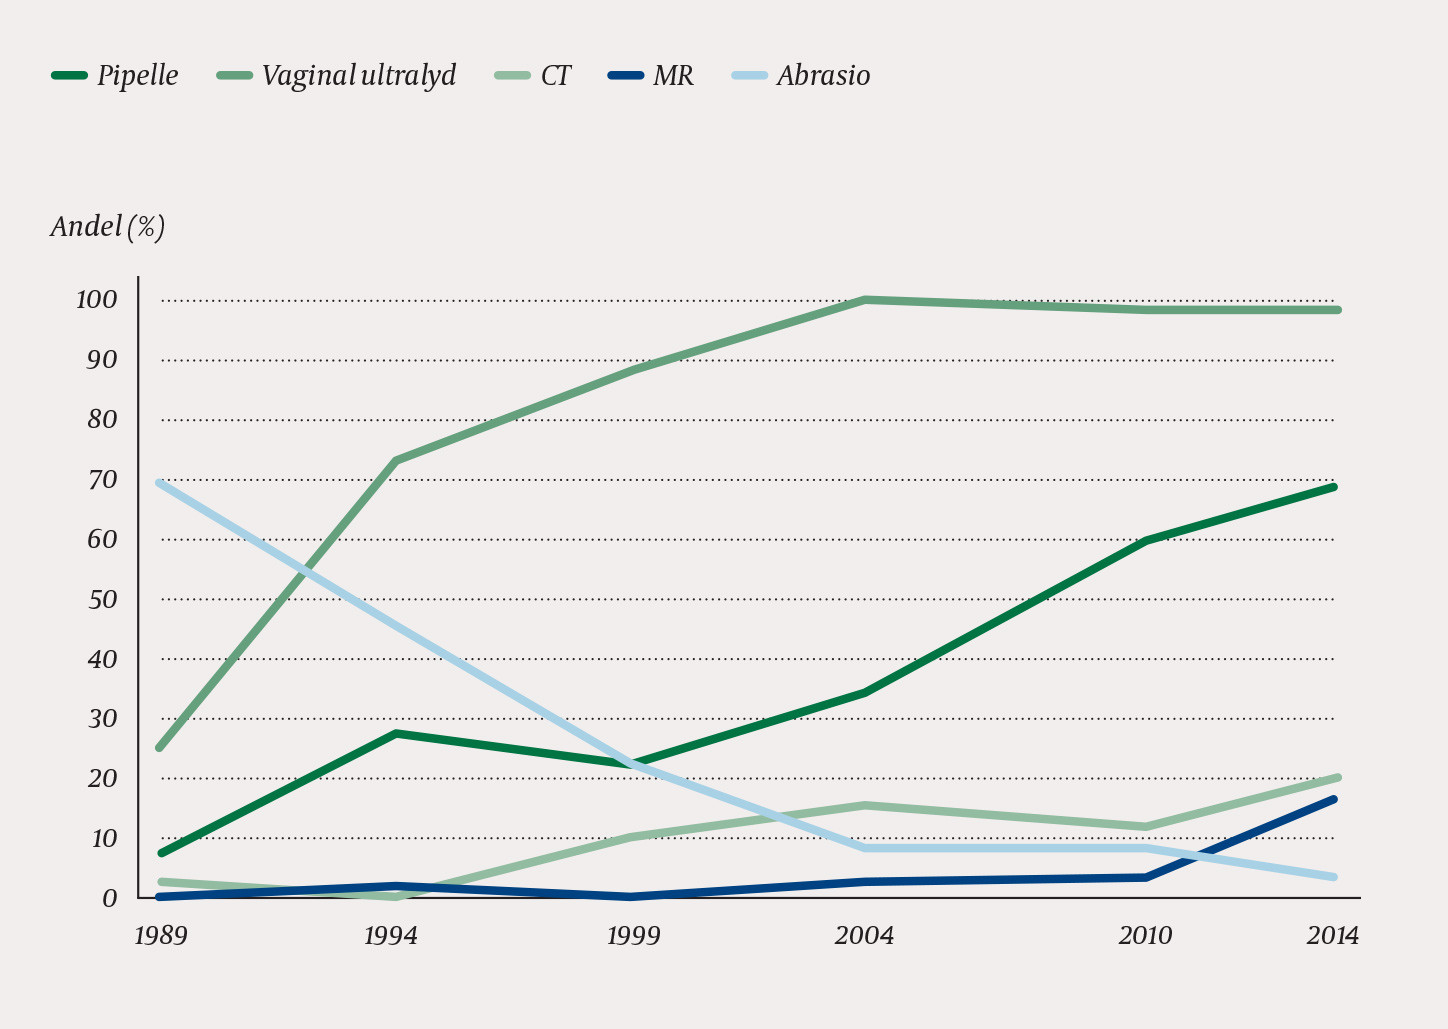

From 1989 to 2014, preoperative diagnosis by dilation and curettage was reduced from 68 % to 4 %, whereas the Pipelle method increased from 8 % to 68 %. In 2014, ultrasound examination was performed in 97 % of patients. While hysterectomies performed with laparotomy fell from 107 in 1989 to 37 per 100 000 women in 2014, vaginal and laparoscopic hysterectomies together increased in the same period from three to 81 per 100 000 women. In 2014, almost half of hysterectomies were performed with robot-assisted laparoscopy. In parallel with the transition from laparotomy to less invasive methods, less bleeding was recorded as well as shorter periods of hospitalization and sickness absence.

Et økende antall kvinner gjennomgikk alternative behandlingsforsøk med endometrieablasjon og/eller hormonspiral før hysterektomi (fig 2). Vi fant økende bruk av bildediagnostikk med CT, MR eller vaginal ultralyd i utredningen. I 2014 ble alle pasientene utredet med bildediagnostikk, de fleste med ultralyd, mot kun 25 % i 1989 (fig 3). Bruk av pipelle for prøvetaking av endometriet har gradvis avløst abrasio, som nå stort sett kun brukes når enkel endometriediagnostikk ikke kan gjennomføres (fig 3).